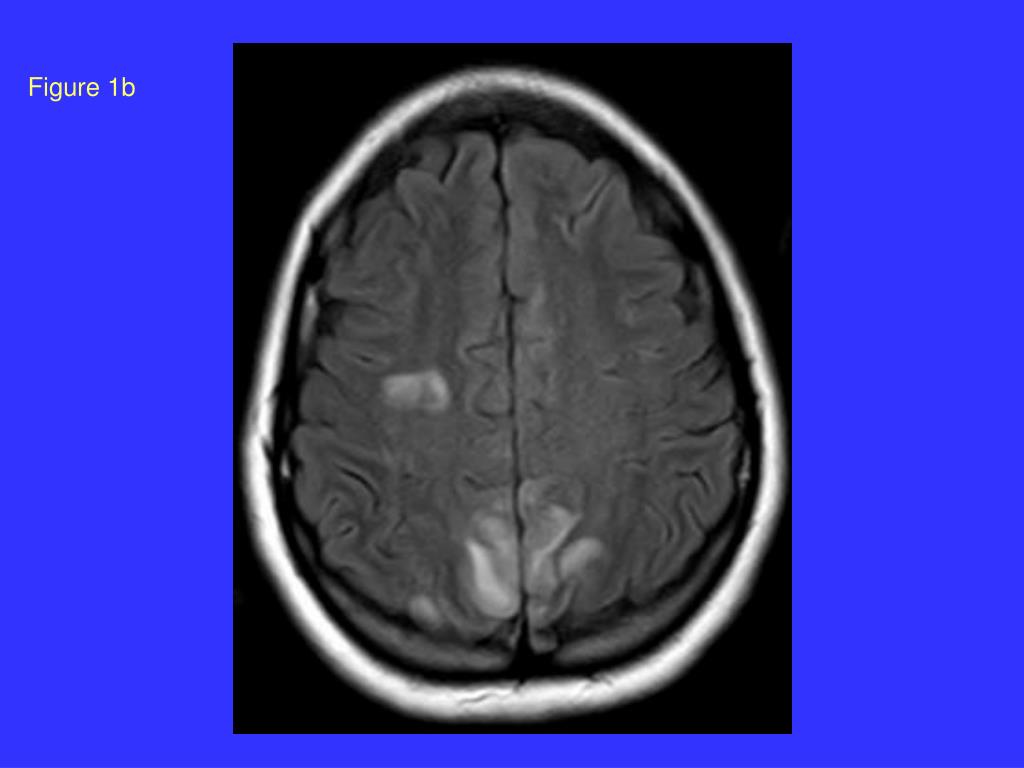

22. Figure 1c

20. Posterior reversible encephalopathy syndrome (PRES): Occipital-parietal cortical and white matter changes in pre-eclampsia. Is this due to capillary damage in the brain? Port JD, Beauchamp RadioGraphics 1998; 18:353-36ı ‘